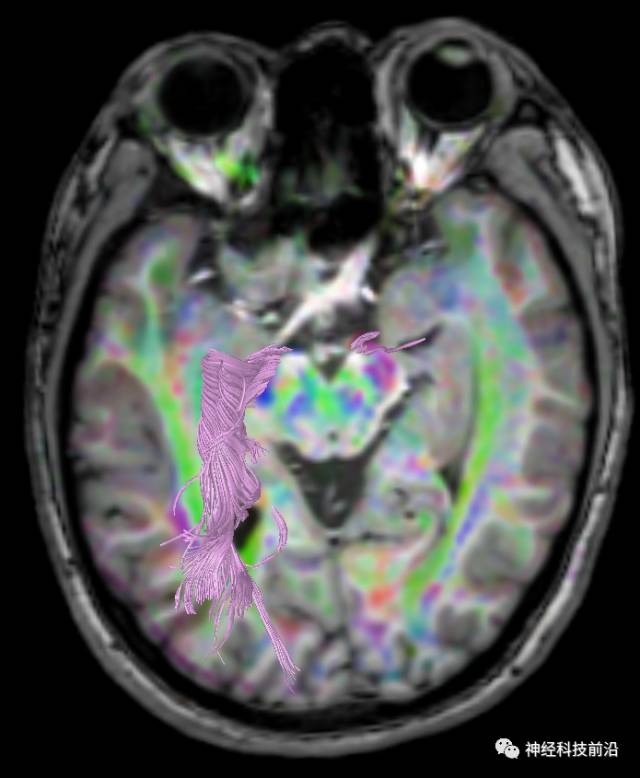

DTI原始图像与T1融合图像

下面为皮质脊髓束的走形及位置

下面为皮质脑桥束的走形方位